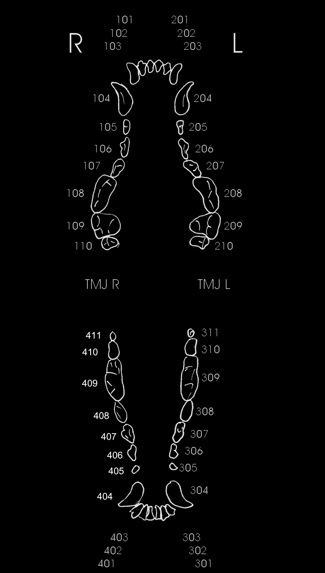

effetti del gioco con pallina da tennis